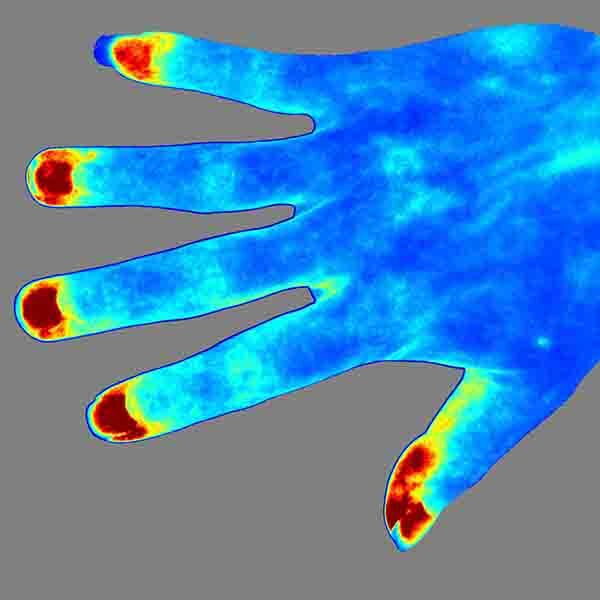

Ультразвуковая визуализация

Ультразвуковая визуализация